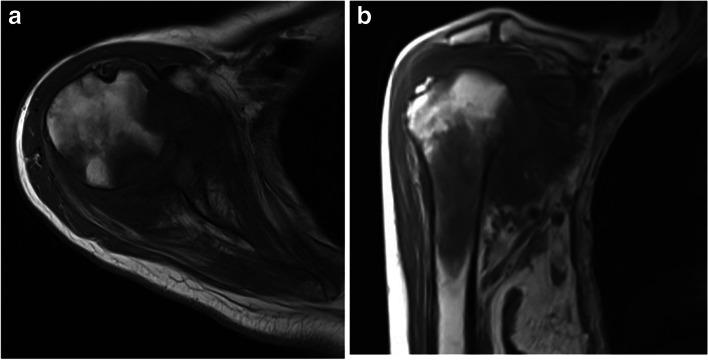

The Prognostic Value of a Novel Magnetic Resonance Imaging-Based Classification for Septic Arthritis of the Shoulder.

J Bone Joint Surg Am. 2020 Aug 5;102(15):1321-1328. doi: 10.2106/JBJS.19.00951.